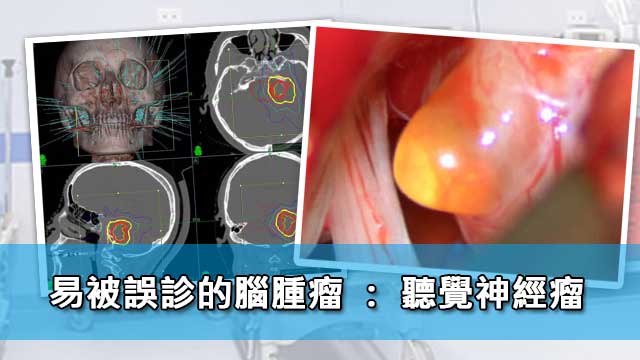

易被誤診的腦腫瘤: 聽覺神經瘤

聽覺神經瘤(Acoustic Neuroma)又稱為聽神經許旺氏細胞瘤(Schwannoma),或前庭神經鞘瘤(Vestibular Schwannoma),是許旺氏細胞瘤沿第8條腦神經線生長所致。聽覺神經瘤佔了所有顱內腫瘤(Brain Tumour)總數約8%。不過在區域性劃分上,聽覺神經瘤在小腦腦橋角(Cerebral – pontine Angle)是常見的腫瘤,大約佔了所有小腦腦橋角區域腫瘤(Cerebral-pontine Angle Tumor)的80至90%。

磁力共振影像診斷

磁力共振醫學影像檢查,有助於明確診斷及鑑別小腦腦橋角區域的腫瘤,例如腦膜瘤、表皮樣囊腫、三叉神經鞘瘤等的鑑別。

考慮微創顯微鏡手術切除

腦神經外科醫生會從多方面考慮及評估,制訂合適的治療方案。若腫瘤體積較細小和沒有症狀時,病人可以用保守治療方案定期覆診及檢查,如腫瘤體積較大又或壓迫到重要神經,病人有症狀及影響都較嚴重時,就要考慮接受微創顯微鏡手術切除。

保護聽覺神經及面部神經的微創顯微鏡手術

一般來說,微創顯微鏡手術切除是根治聽覺神經瘤的方法,但由於腫瘤與神經線和腦幹的緊密關係,手術過程有一定風險,尤其是聽覺神經受損導致聽力喪失,或是面肌神經受損以致面癱的可能性較大。然而經驗豐富的腦神經外科醫生會在顯微鏡下,以熟練精巧的手術,並利用手術中持續神經監測系統(Continuous Intraoperative Neural Monitoring System IOM),大大提高聽覺神經及面肌神經的功能保存。經驗豐富的腦神經外科醫生,腫瘤全切率達97至100%,面肌神經的功能保存率為51至98.2%,聽力保存率為19至40%,腫瘤復發率為5至10%。